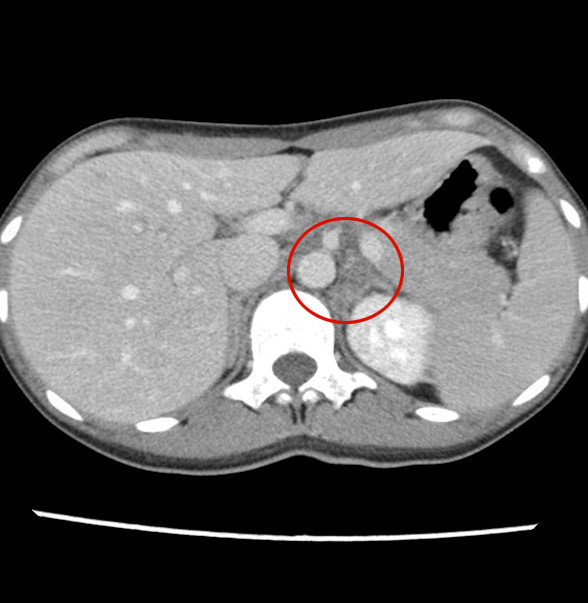

- 【参考症例② 44歳女性】

- 両側の副腎腫大

- 周囲の脂肪織濃度上昇

- 副腎の造影不良

- 形態は比較的保たれている。

造影CT 動脈相

造影CT 平衡相